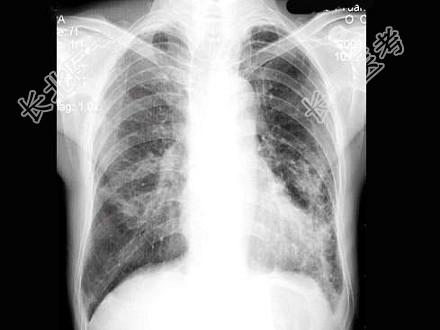

- 单项选择题男,66岁, 咳嗽、发热2周余,无痰中带血, X线检查如图,最可能的诊断是 ( )

A、细支气管肺泡癌

B、血行播散型肺结核

C、左肺浸润型肺结核

D、左肺炎症

E、肺转移瘤